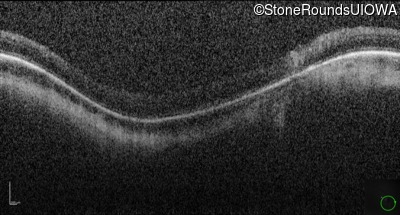

Optical Coherence Tomography - Right - 10/160 sc

Exemplar / OCT Stack

OCT Stack